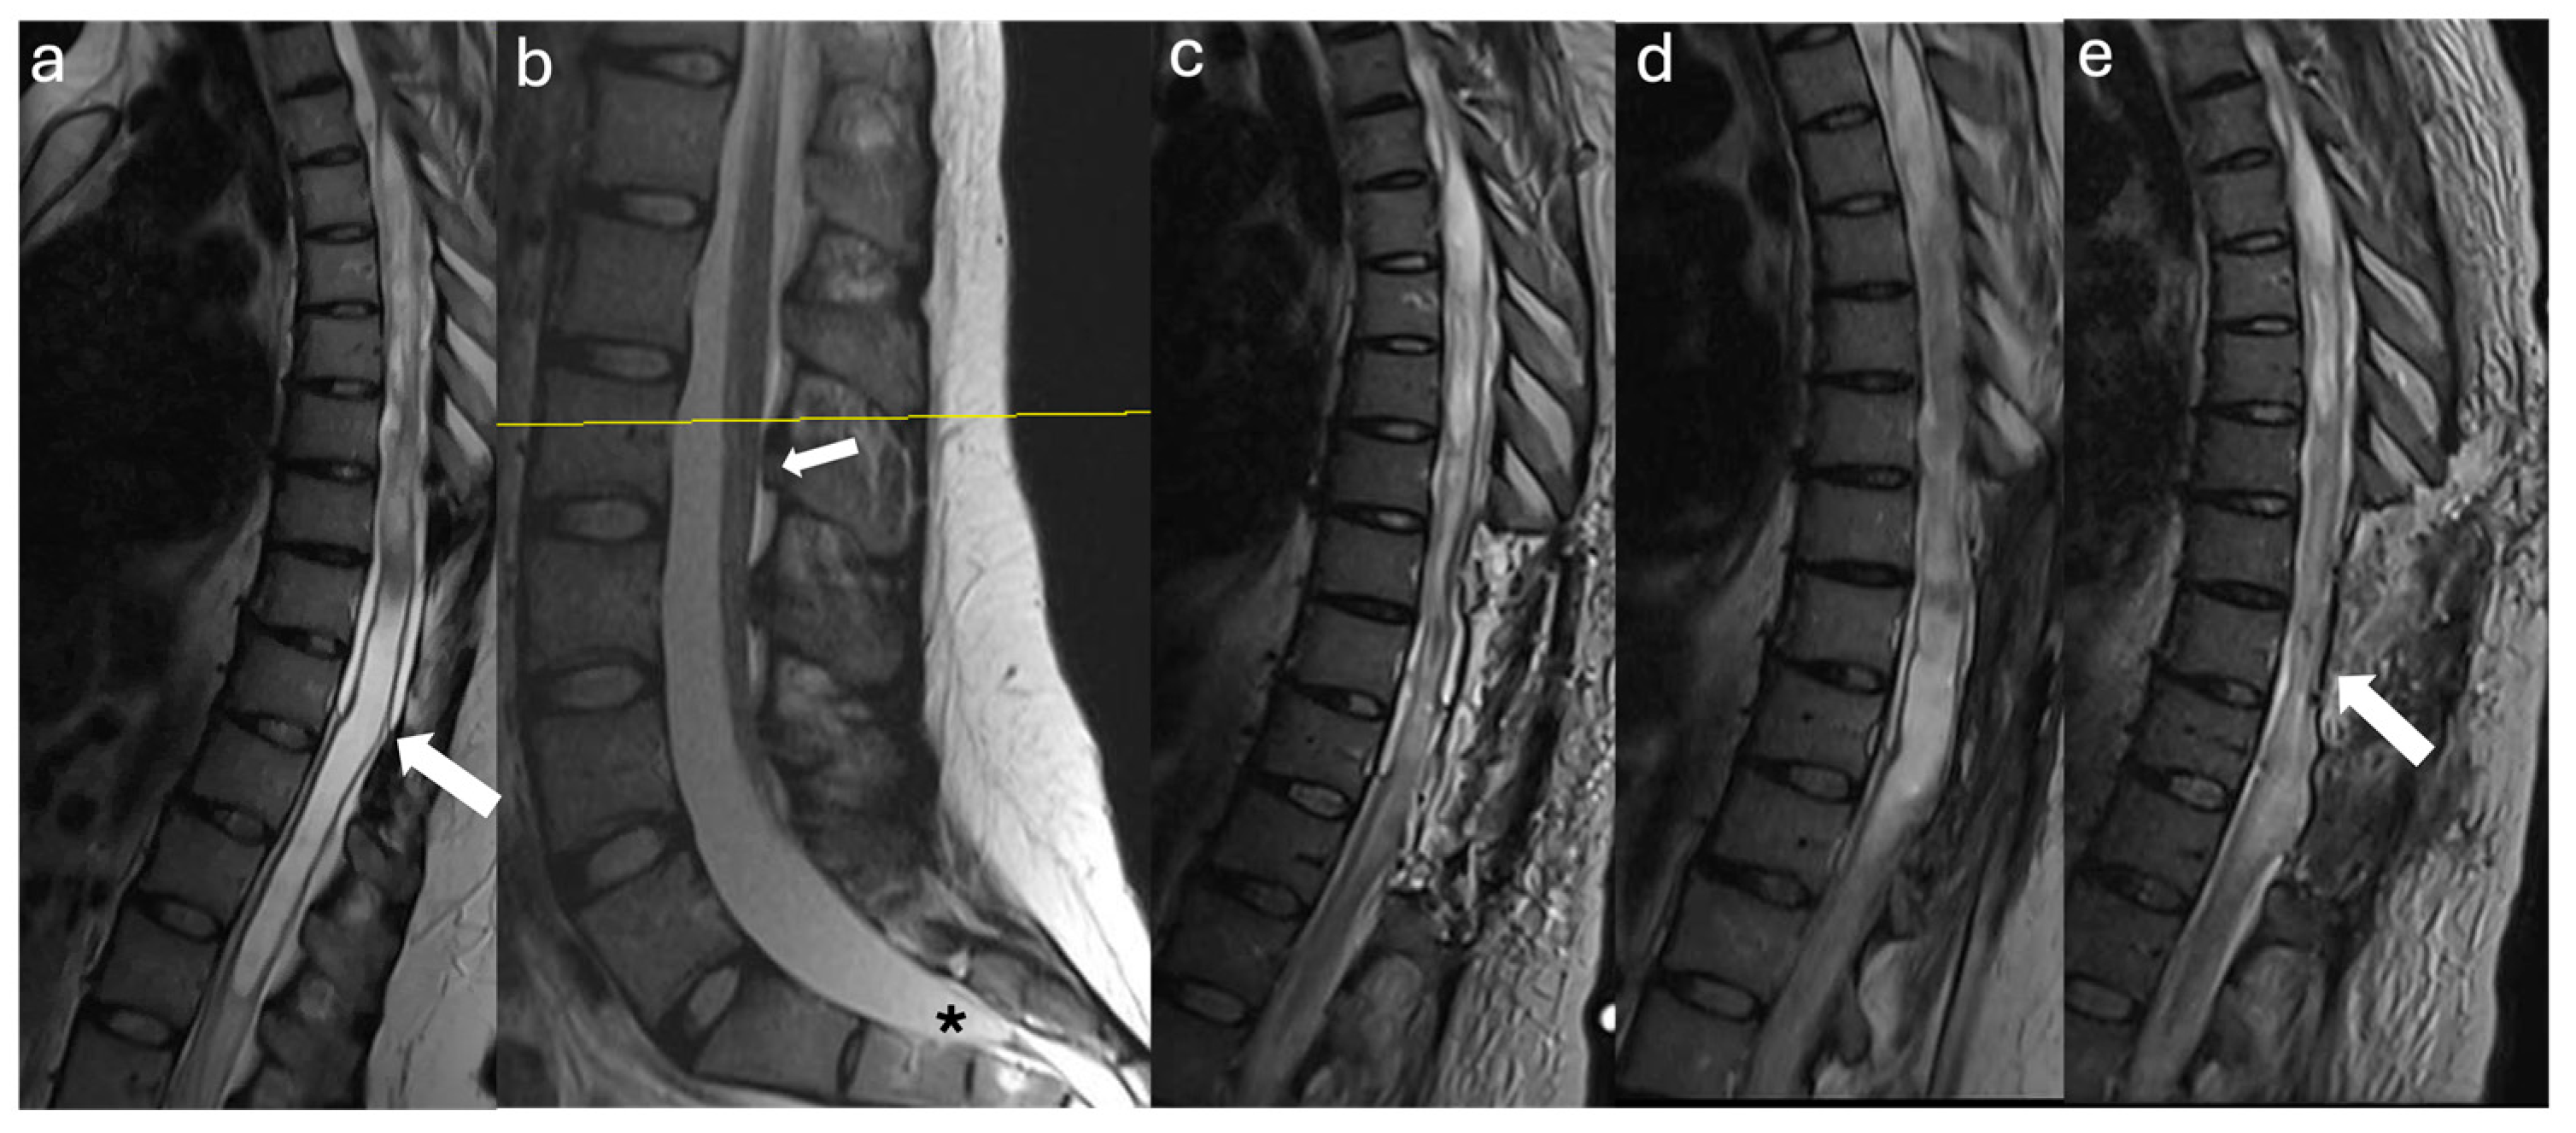

3.2.1. Case #1

3.2.2. Case #2

3.2.3. Case #3

3.2.4. Case #4

3.2.5. Case #5